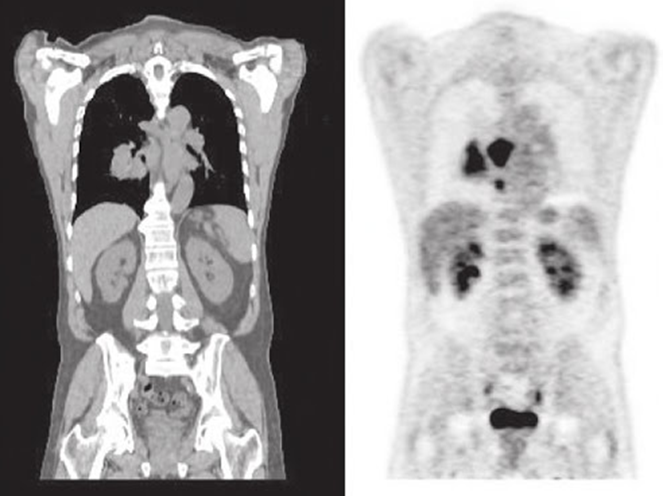

CT left and PET right

this scan shows what

abnormal distribution in the right lung = lung cancer